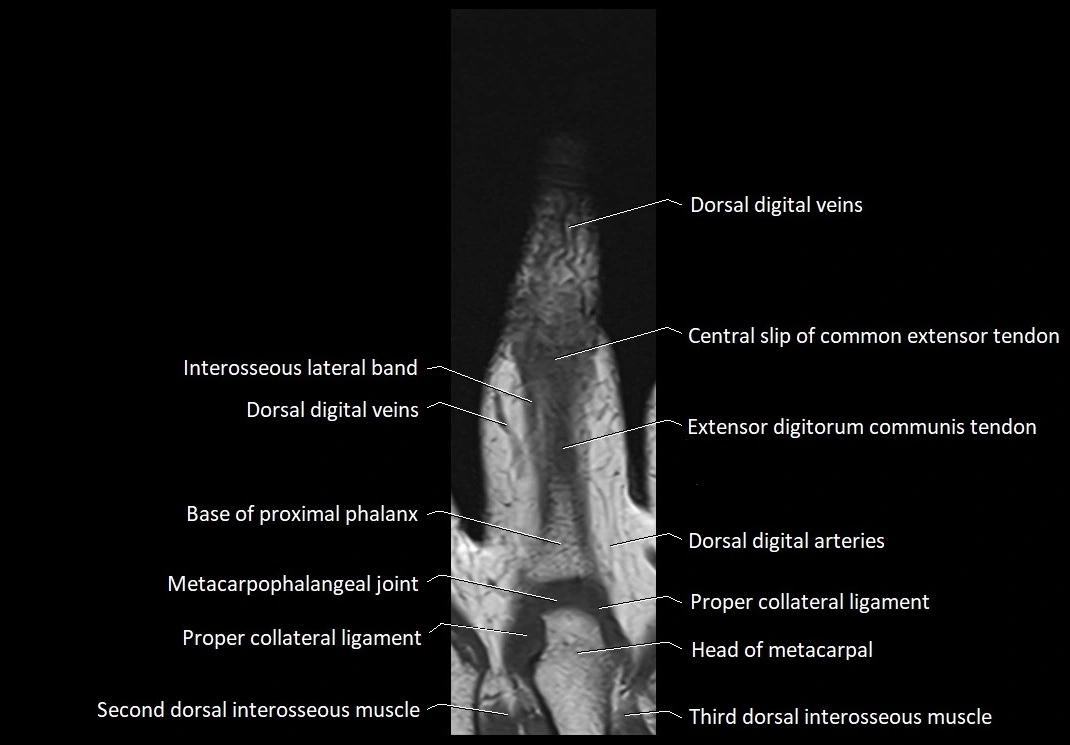

- Central slip of common extensor tendon

- Dorsal digital arteries (hand)

- Dorsal digital veins (hand)

- Head of metacarpal bone

- Interosseous lateral band

- Metacarpophalangeal joints

- Proper collateral ligament

- Second dorsal interosseous muscle of hand

- Third dorsal interosseous muscle of hand